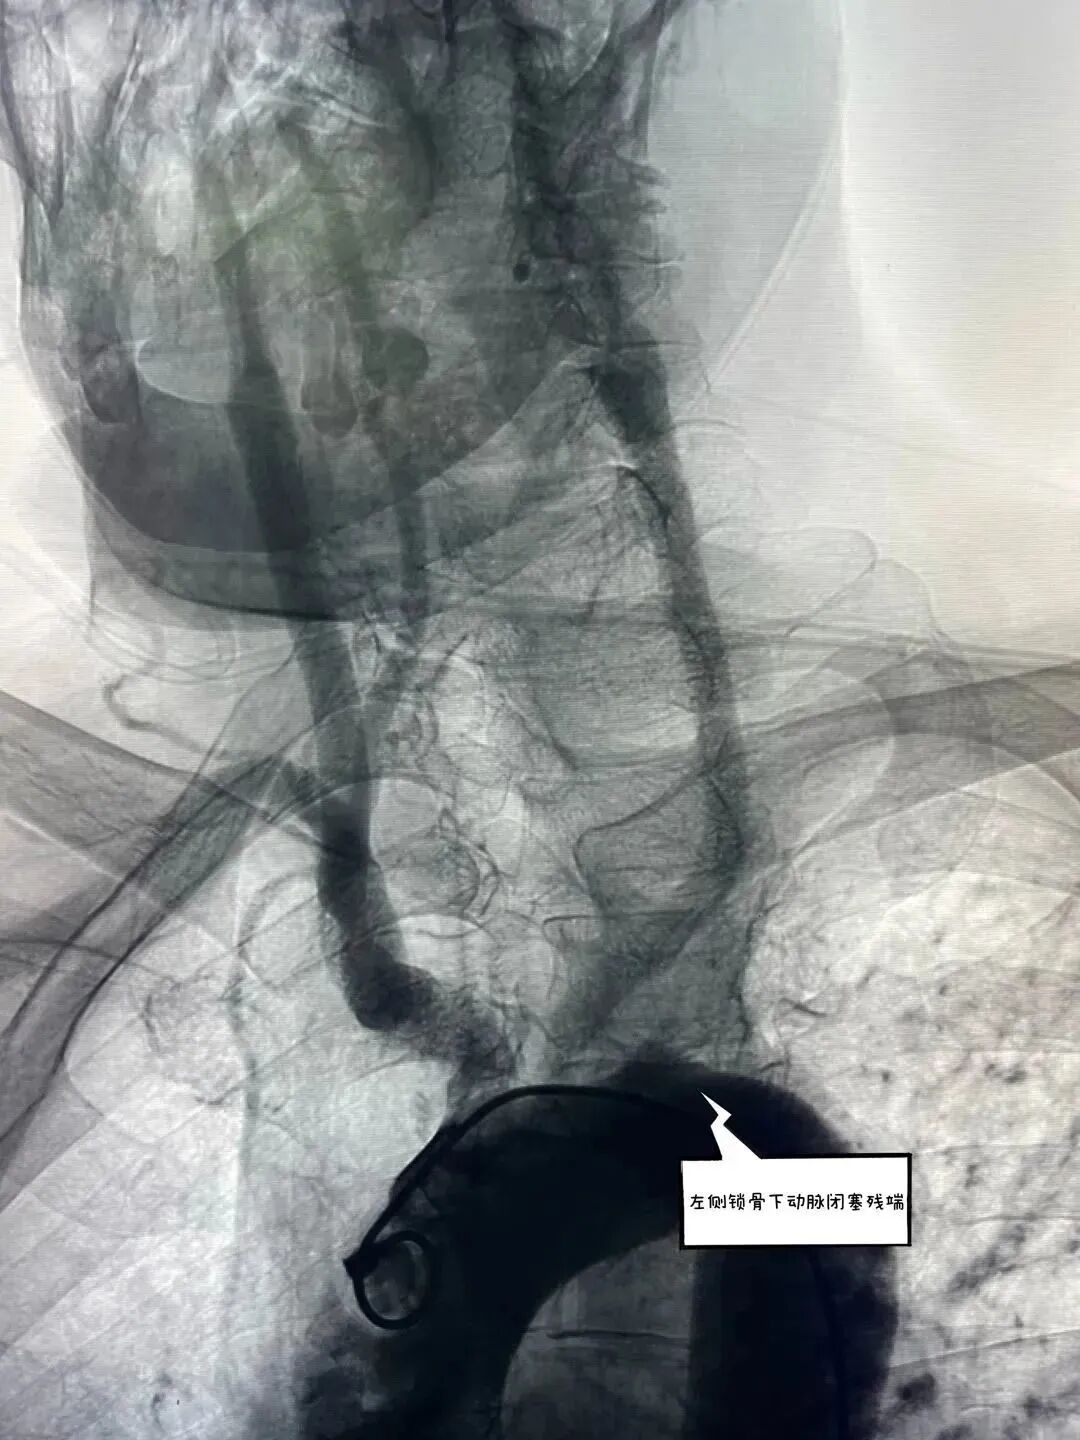

主动脉弓造影提示左侧锁骨下动脉未见显影      经桡动脉逆向造影寻找血管真腔